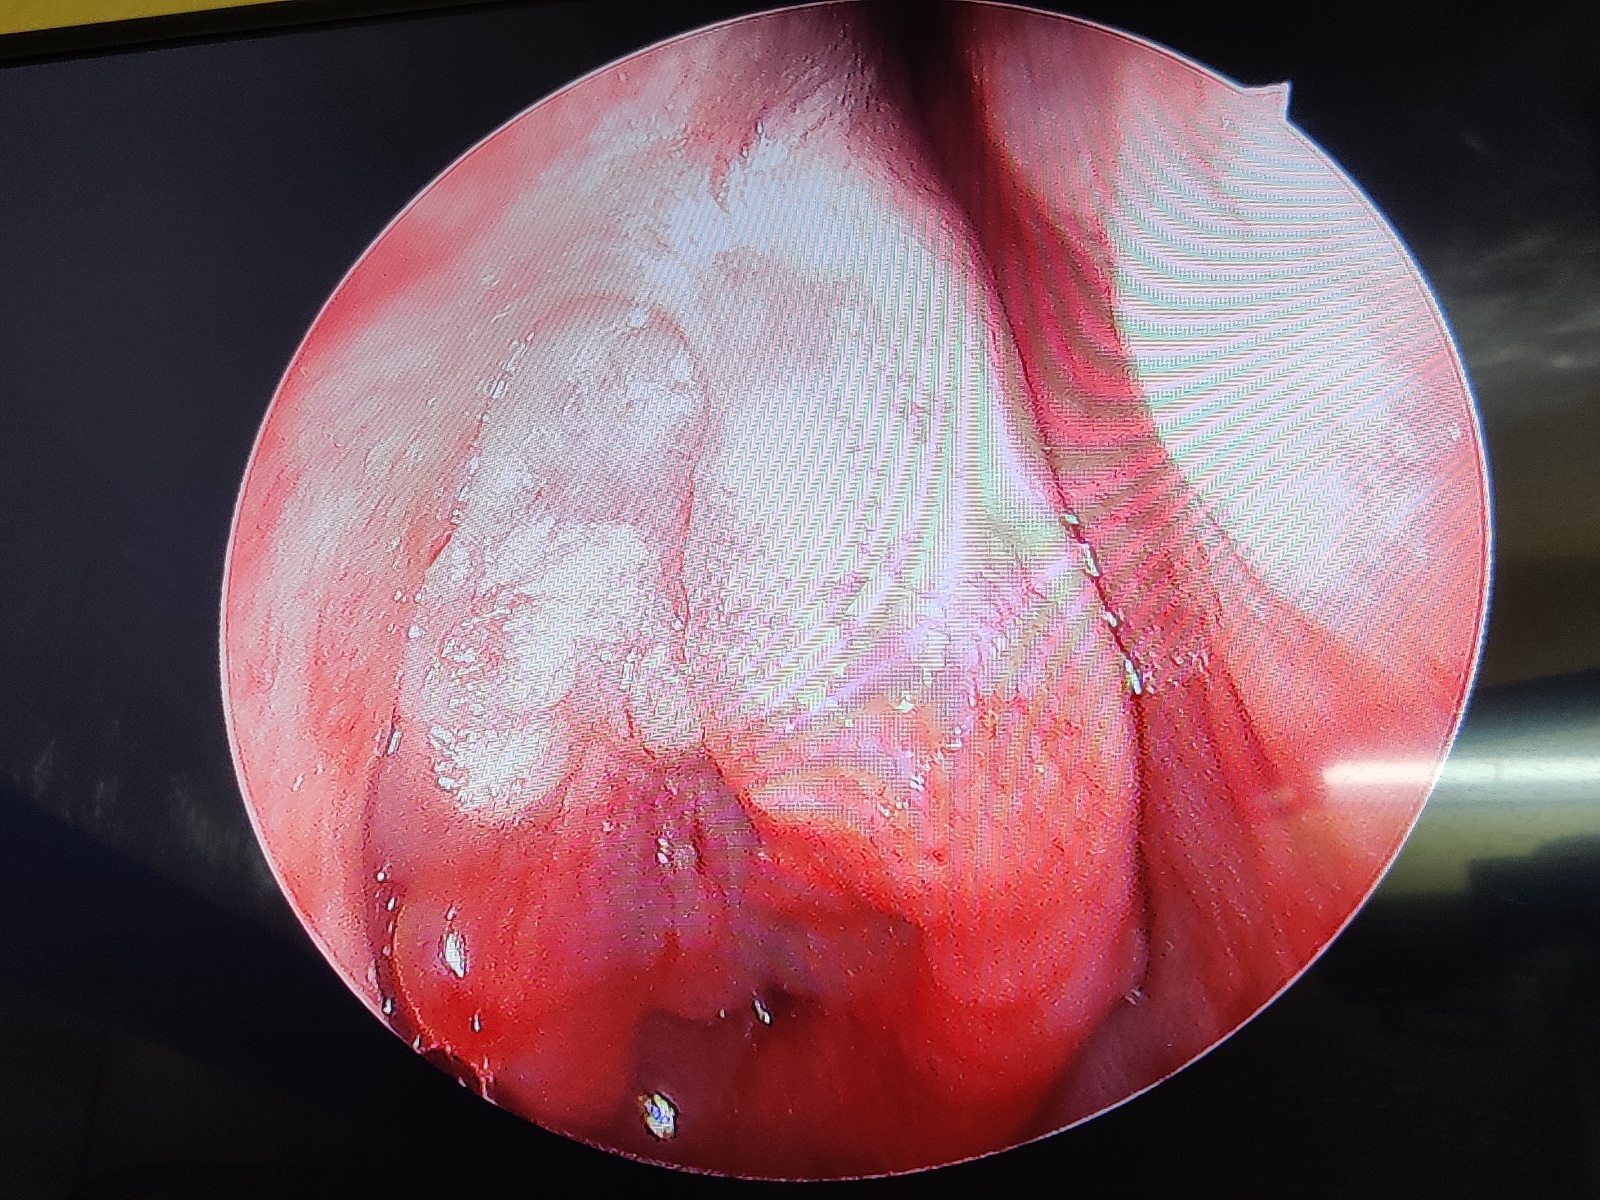

Nasal Endoscopy in Nagpur, Nasal Endoscopy near me...